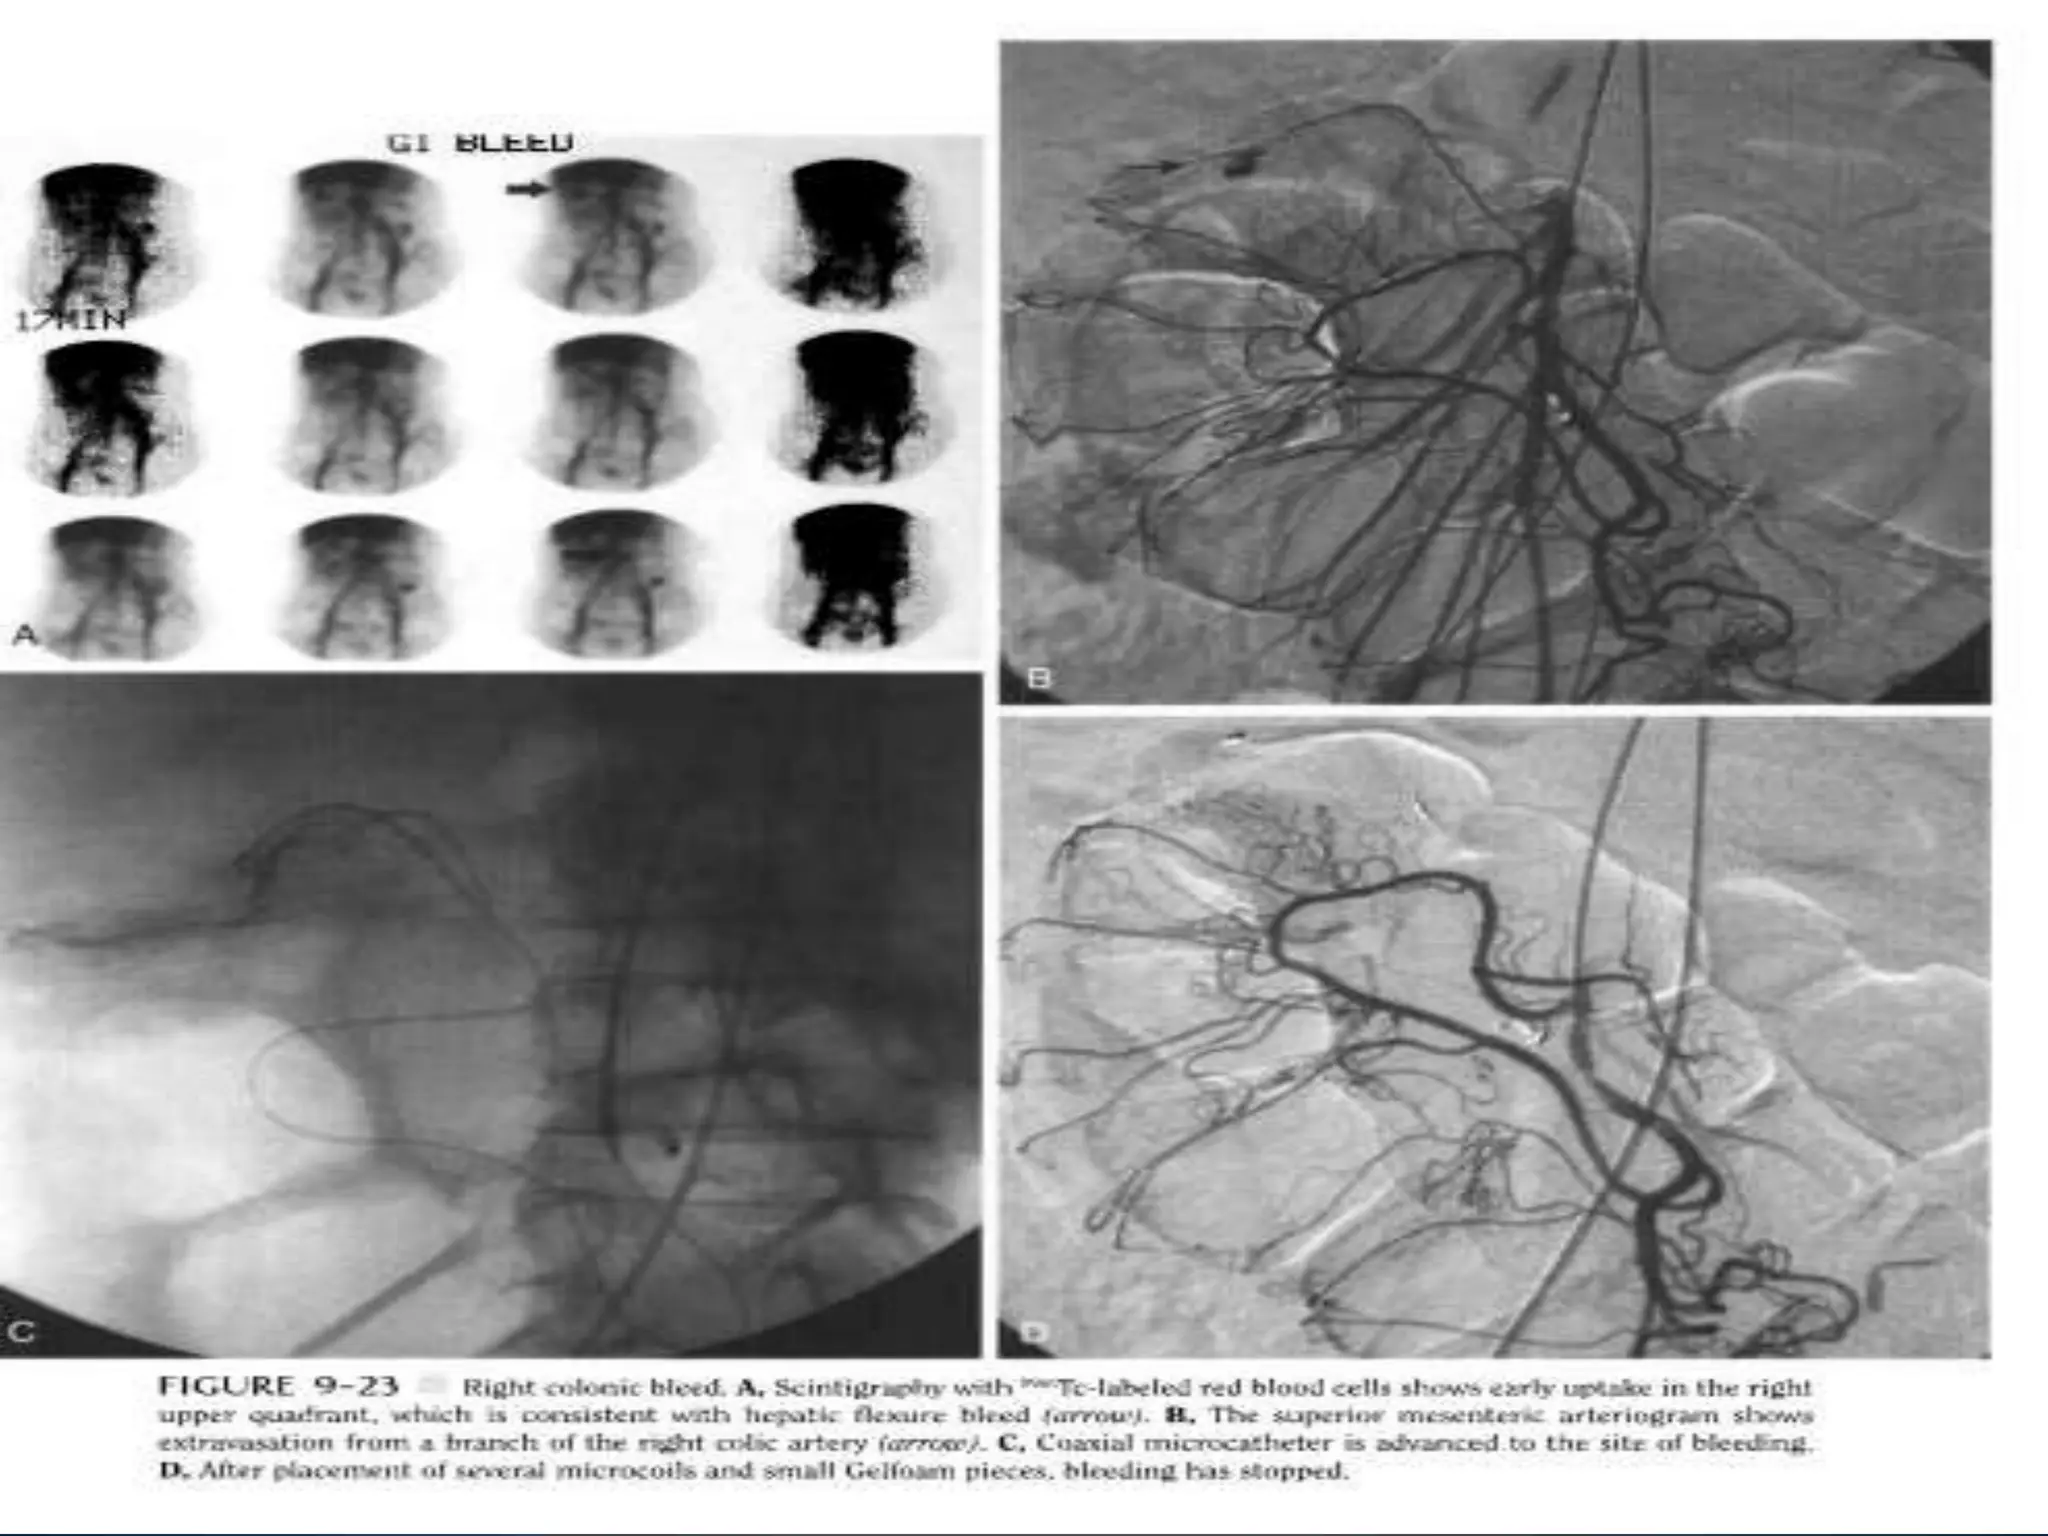

• Scintigraphy is done with 9"Tc- sulfur colloid or 99mTc-labeled

red blood Cells.

• The thresh- old for detection of gastrointestinal bleeding is

quoted as ranging from 0.05 to 0.4 ml minute, compared with a

rate of about 0.5 ml minute with angiography.

• Most centers prefer red blood cell scanning over sulfur colloid

scanning. Red blood cell scans are more sensitive, avoid

significant background activity over the liver and spleen, and

can show intermittent bleeding through delayed imaging

• The Scintigraphy imaging suffers from a low specificity (50%) due

to its limited resolution

• Both methods can localize the bleeding site.

However, forward or backward movement of tracer in

the bowel can mislead the reader.

• Patients with negative scan results are observed.

Patients with positive scan results should undergo

immediate angiography